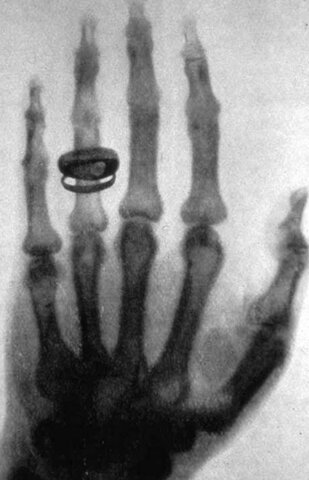

• La primera radiografía

La primera radiografía

Roentgen toma una radiografía a la mano de su esposa Bertha Roenttgen.